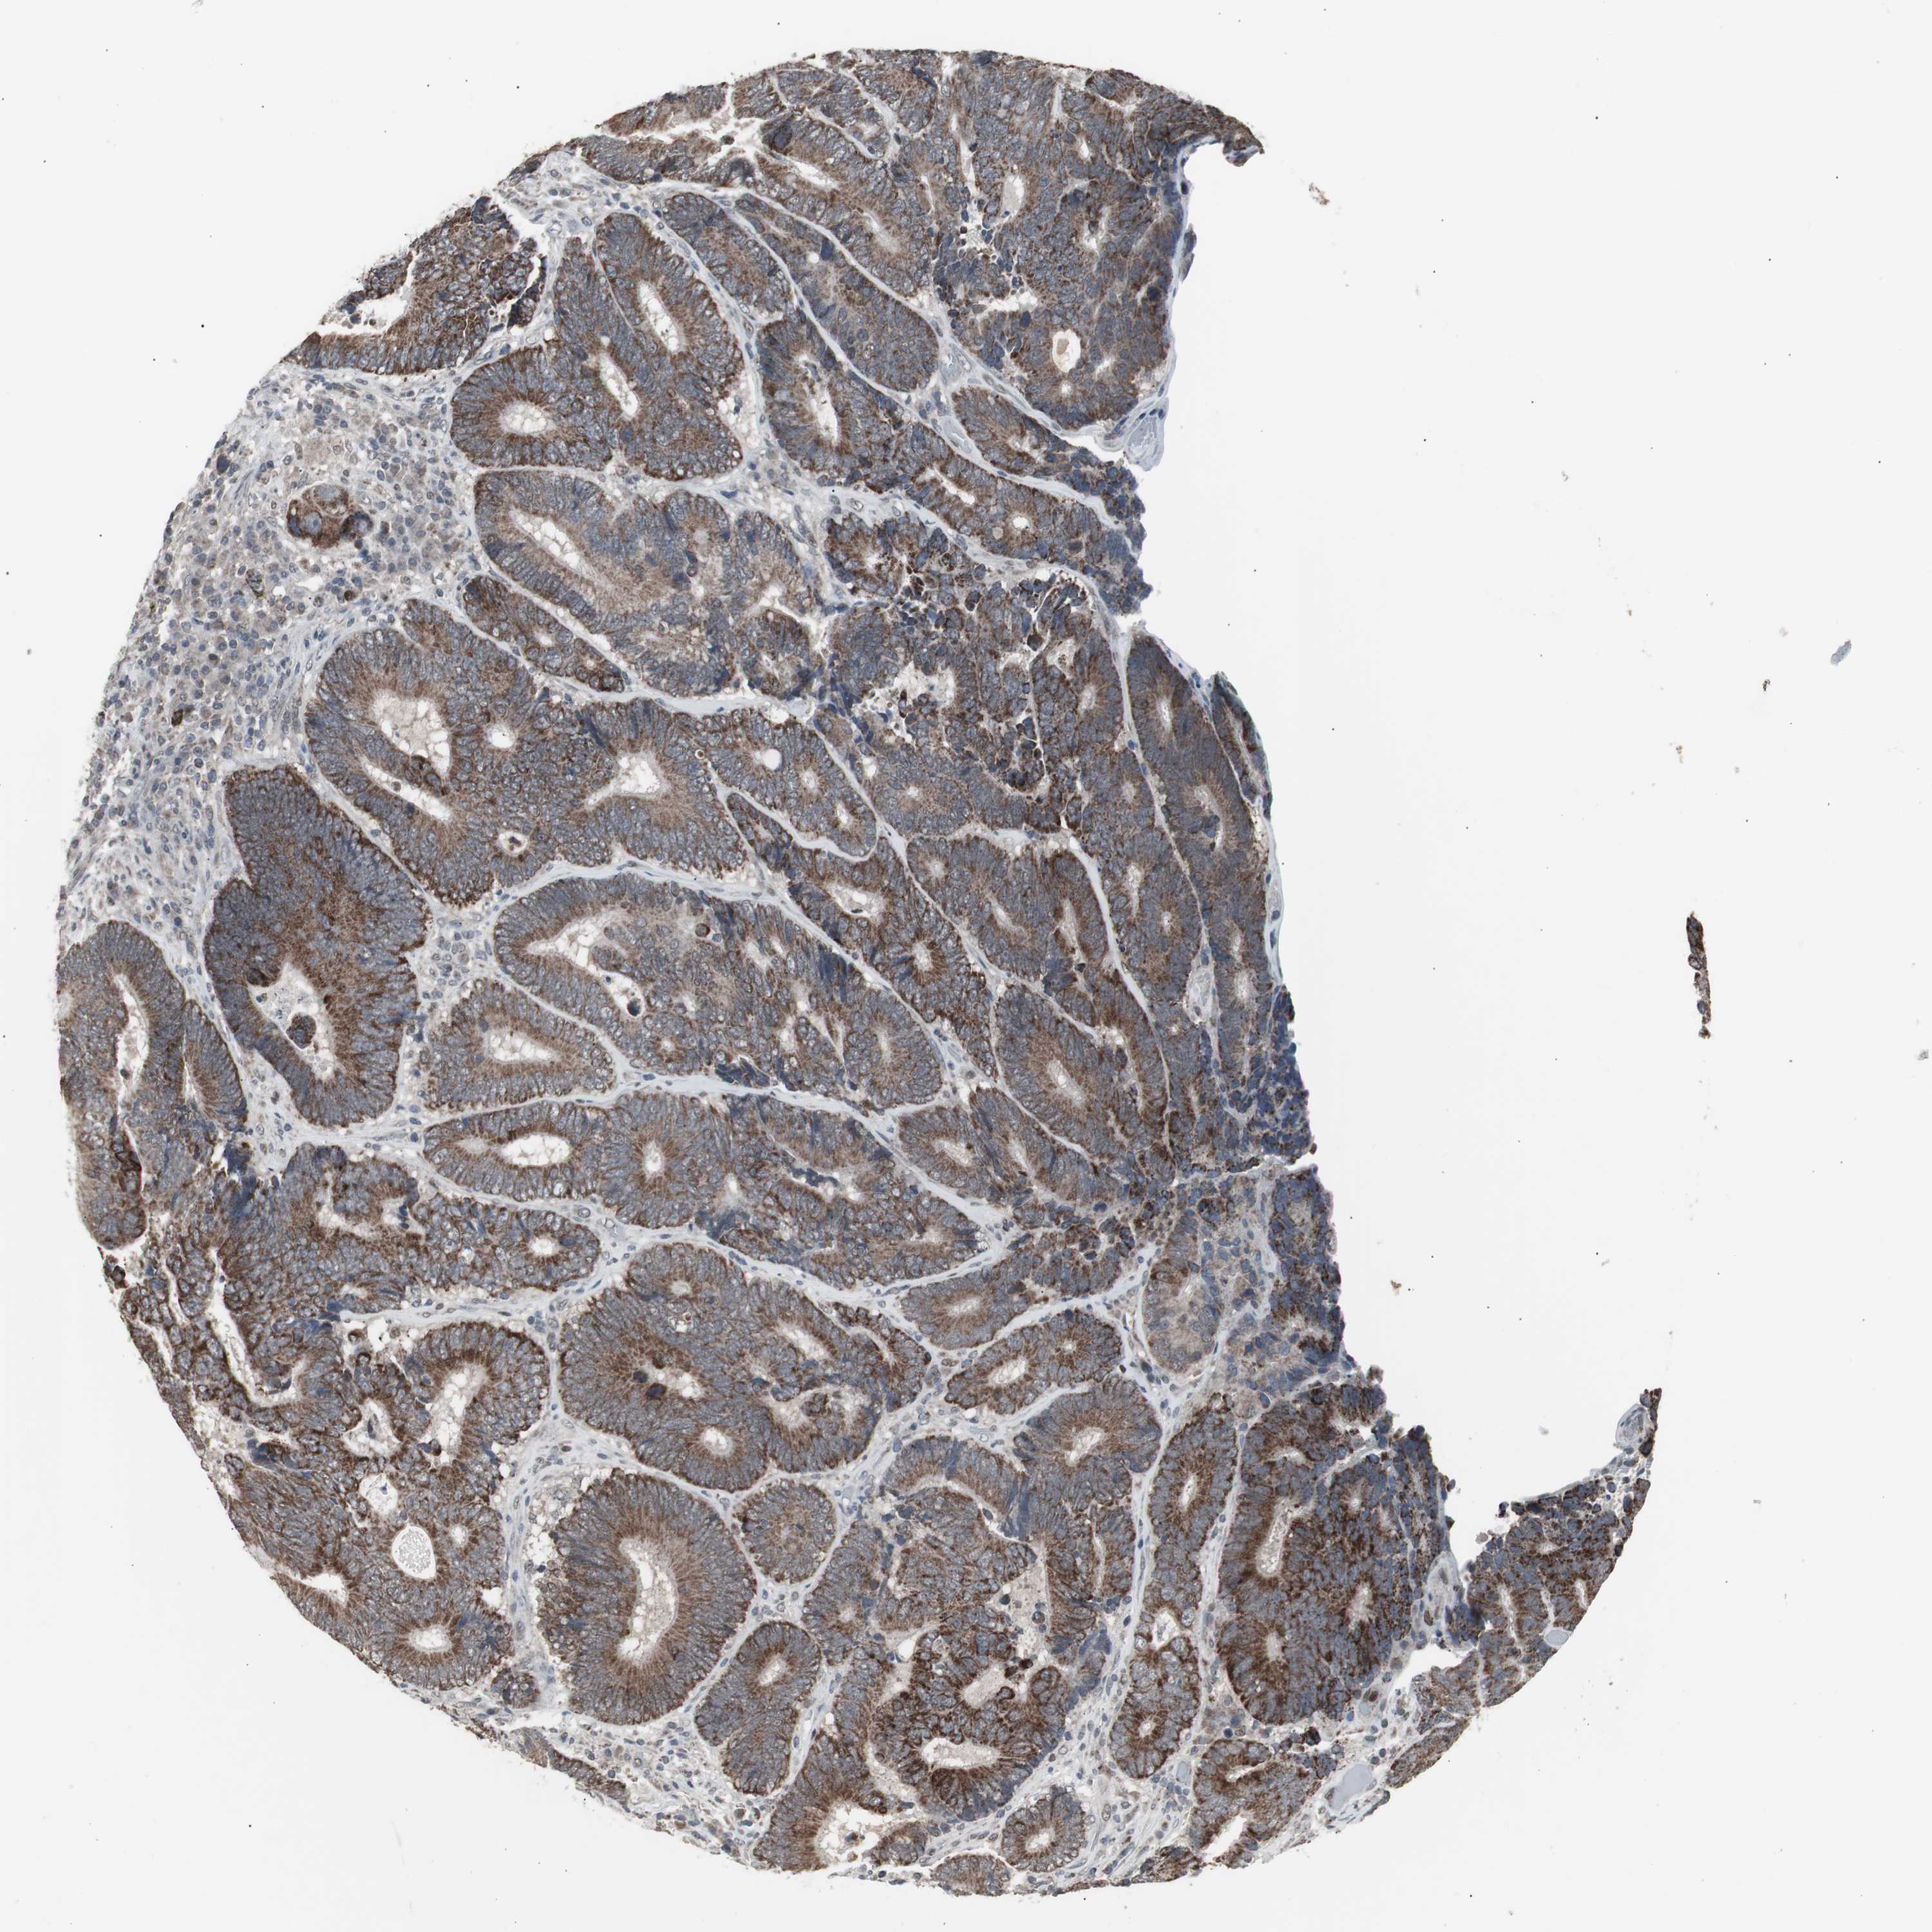

Colorectal cancer

Colon adenocarcinoma

Average pTPM 18.6

Number of samples 254